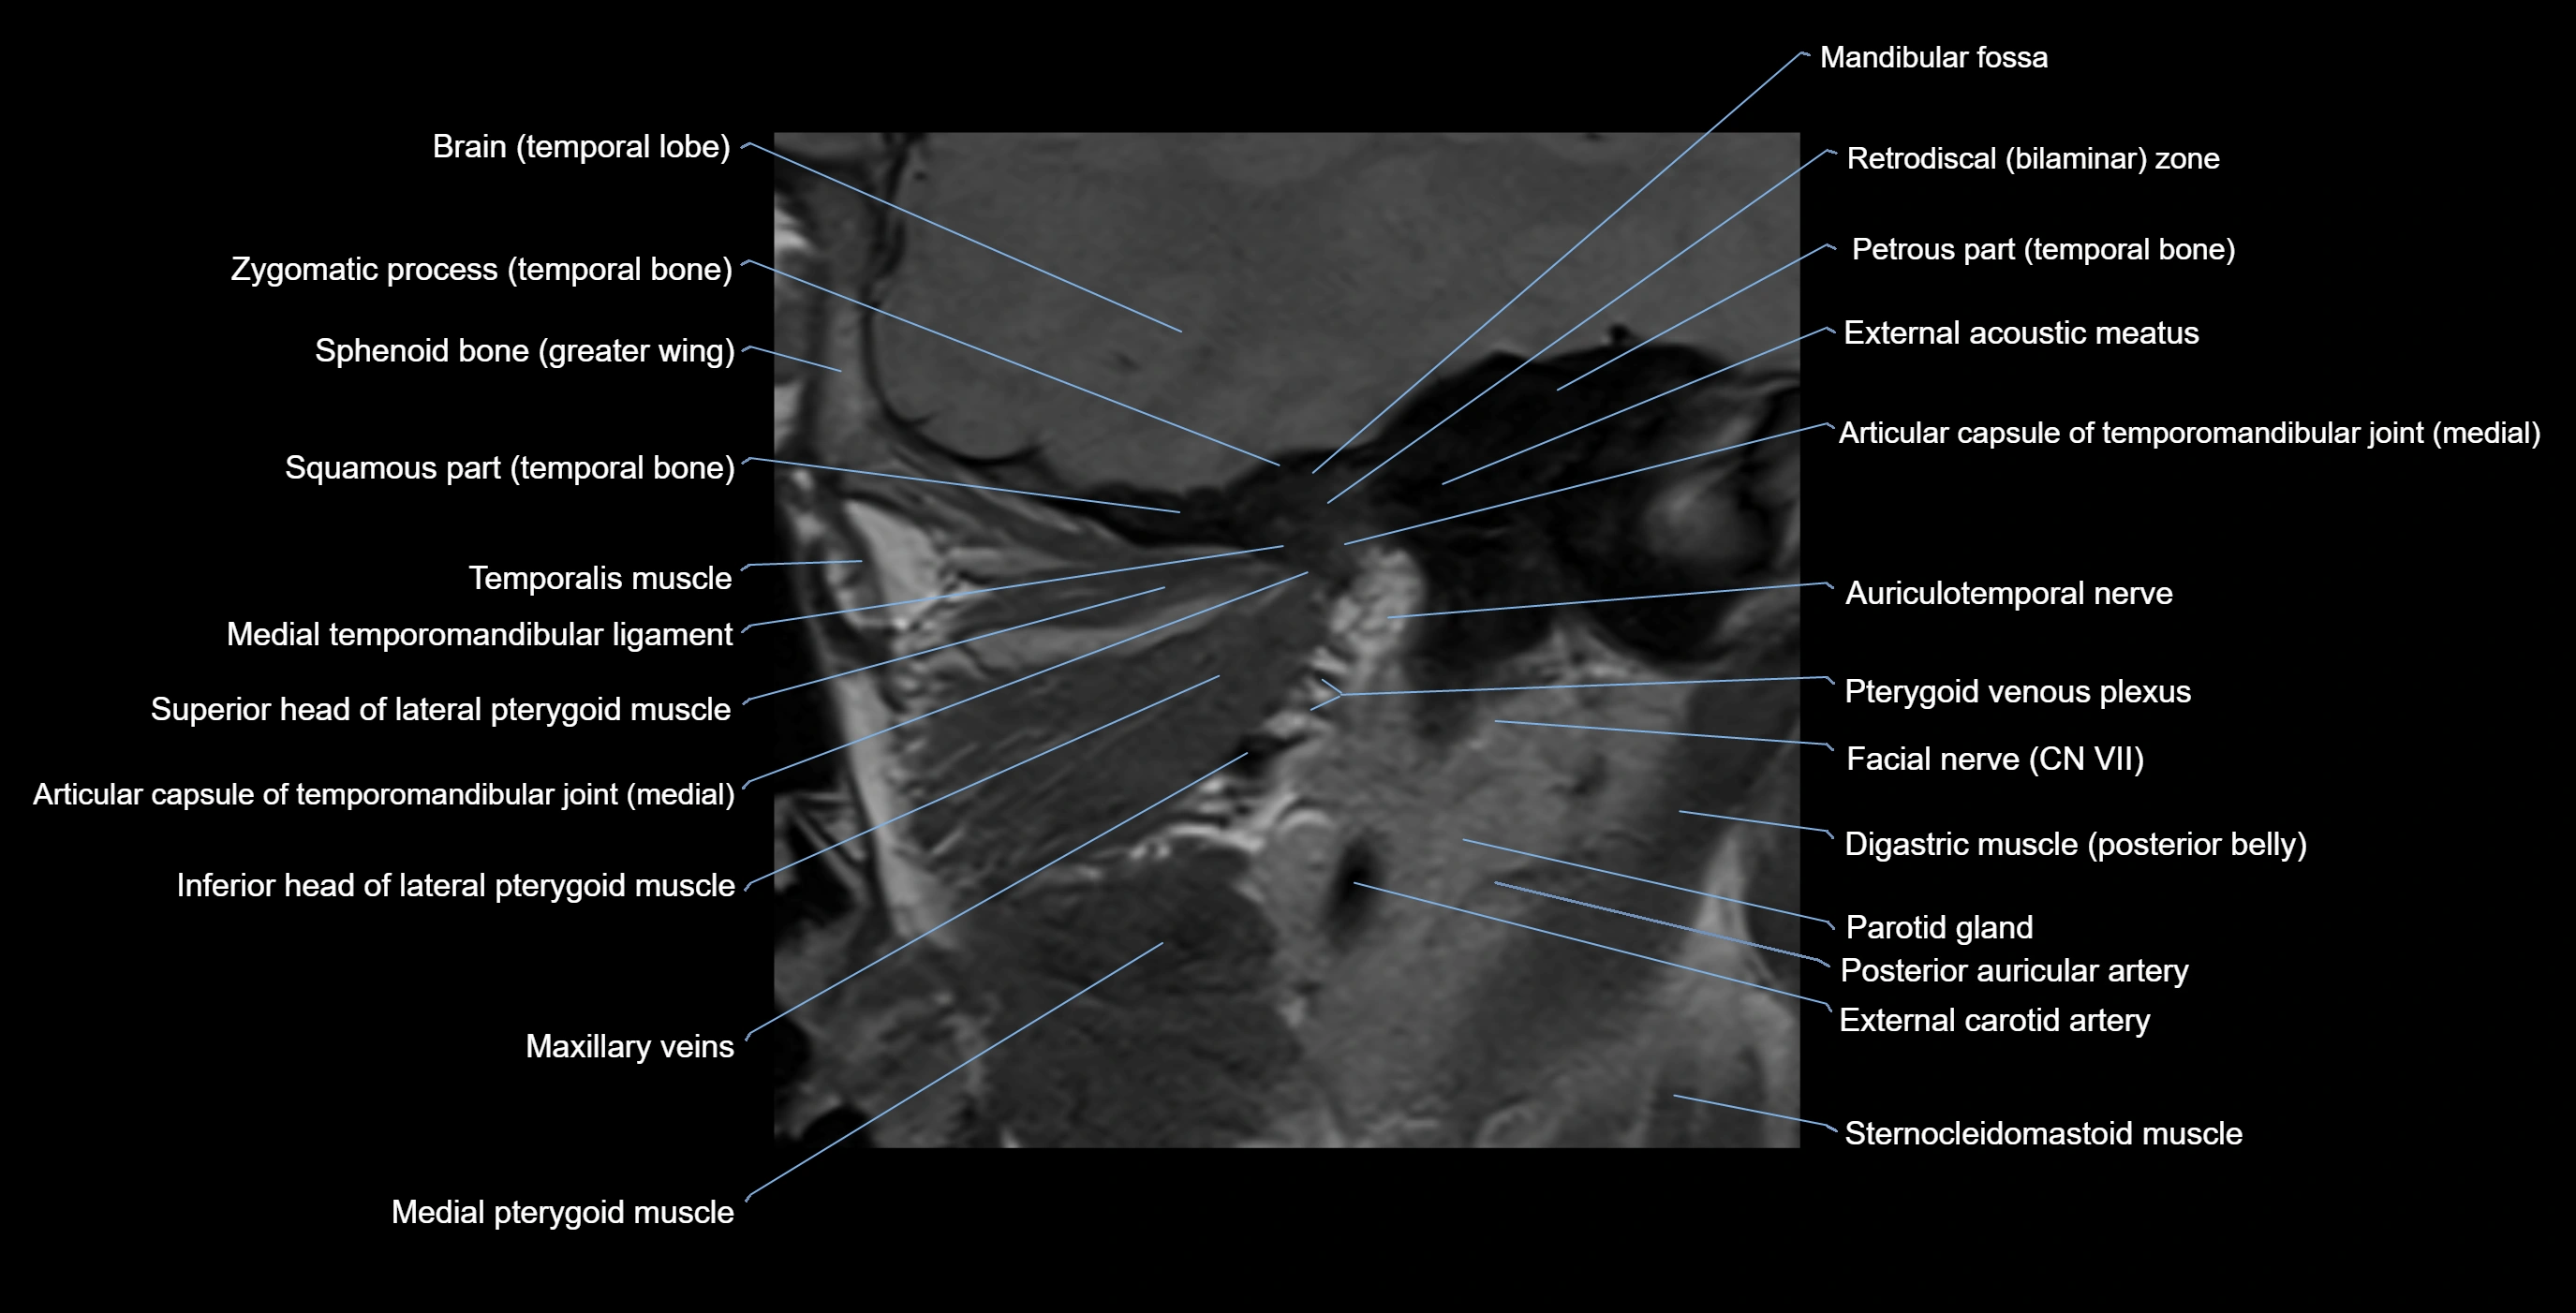

MRI appearance

T1-weighted images:

• Cortical bone: Low signal intensity

• Cancellous marrow: Intermediate to high signal depending on fatty content

• Teeth: Signal void structures

• Adjacent soft tissues: Normal gingiva and oral mucosa signal

T2-weighted images:

• Cortical bone and teeth: Low signal

• Marrow: Intermediate signal